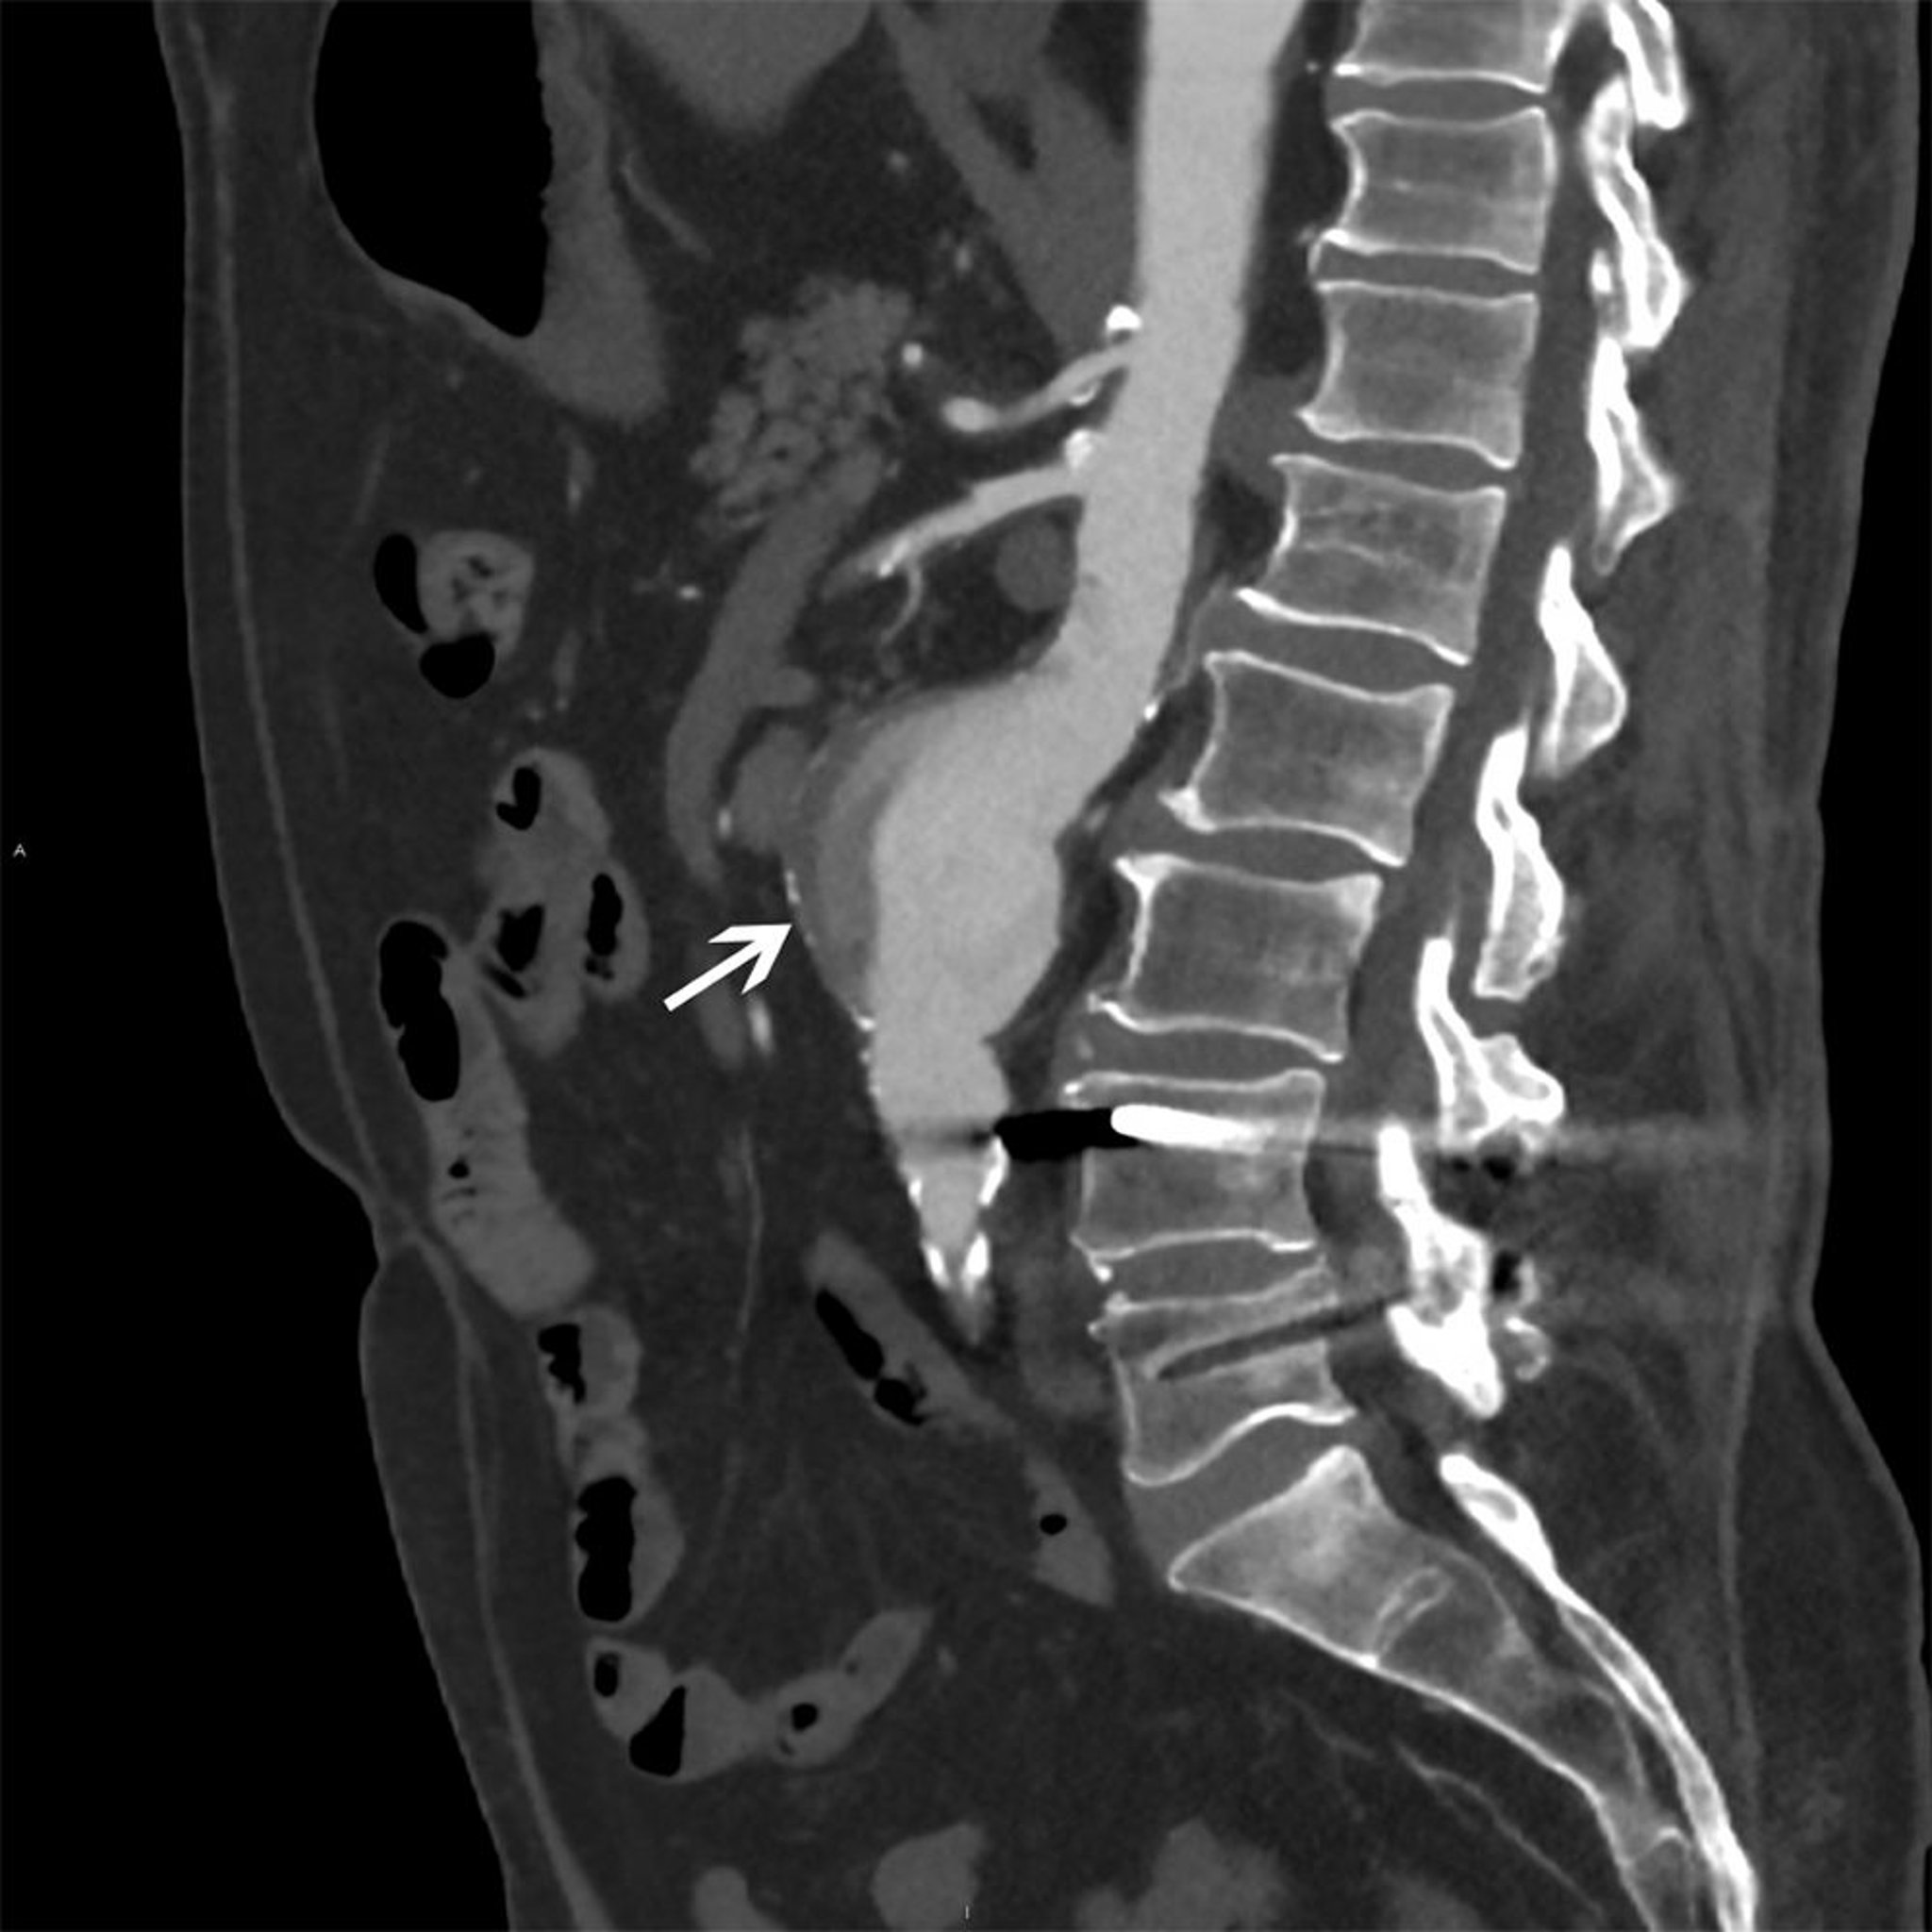

Mũi tên màu trắng cho thấy một phình động mạch chủ bụng có kích thước 5 cm với dòng chảy không đồng nhất và mảng bám trên thành.

© 2017 Bác sĩ Elliot K. Fishman.